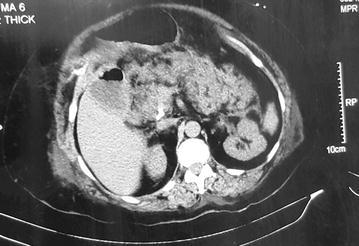

A 58 year old lady was admitted to our unit with acute onset epigastric pain and vomiting for 4 h duration. Following admission she complained of retrosternal tightening type of a chest pain. She had elevated serum amylase and cardiac troponin. Electrocardiogram (ECG) revealed lateral ischaemia. Contrast computerized tomography abdomen revealed acute severe necrotizing pancreatitis.

一名58岁女性因突发上腹部疼痛和呕吐4小时入院。入院后,她主诉胸骨后压榨样胸痛。血清淀粉酶和心肌肌钙蛋白升高。心电图(ECG)显示侧壁缺血。腹部增强CT显示急性重症坏死性胰腺炎。